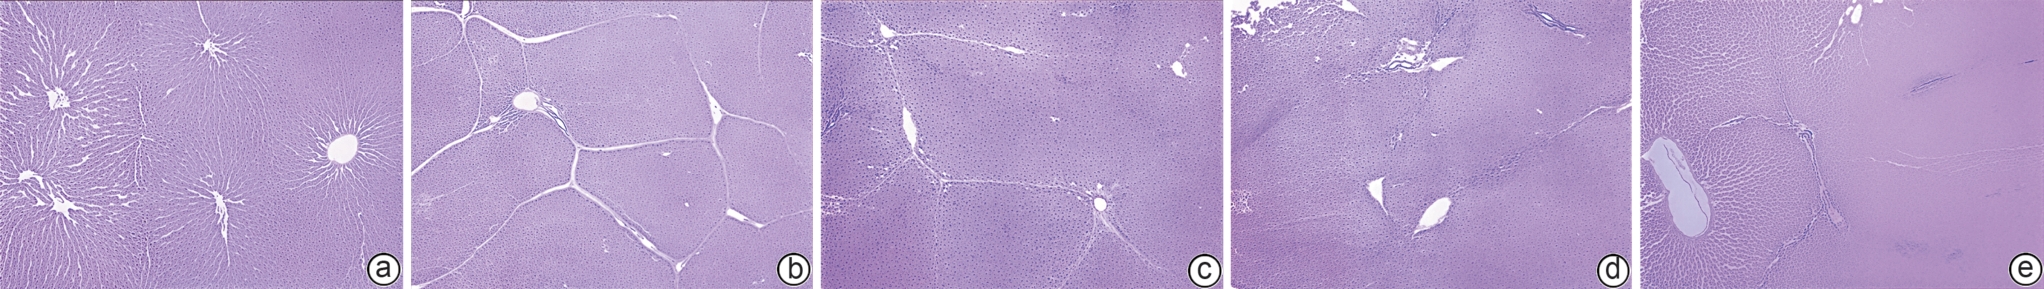

胸腺素β4对四氯化碳诱导的肝纤维化小鼠模型的影响及其作用机制

朱耘函, 王思琪, 景登娅, 冯勤颖

2026, 42(3): 593-599. DOI: 10.12449/JCH260314

摘要:

目的  本研究拟探讨胸腺素β4(Tβ4)通过调控血小板衍生生长因子(PDGF)表达及诱导肝星状细胞(HSC)凋亡,对四氯化碳(CCl4)诱导的肝纤维化小鼠模型的干预作用与潜在机制,为临床抗肝纤维化治疗提供新的实验依据。  方法  选取30只雄性C57小鼠,随机分为正常对照组、模型组,以及Tβ4低(3 mg/kg)、中(6 mg/kg)和高(12 mg/kg)剂量治疗组,每组6只。正常对照组自由摄食普通饲料,其余各组腹腔注射50% CCl4与橄榄油混合液建立肝纤维化模型,经超声及病理学验证造模成功后,对各治疗组小鼠连续皮下注射Tβ4干预4周。实验结束后取肝组织行苏木精-伊红及Masson染色观察组织病理变化,应用实时荧光定量聚合酶链反应检测血PDGF mRNA表达,原位末端转移酶标记(TUNEL)法检测HSC凋亡情况。计量资料多组间比较采用单因素方差分析,进一步两两比较采用LSD-t检验。  结果  与模型组比较,Tβ4中、高剂量治疗组小鼠肝纤维化程度均呈现不同程度的减轻。实时荧光定量聚合酶链反应结果显示,Tβ4可显著下调肝组织中PDGF mRNA表达,各剂量治疗组间差异有统计学意义(P<0.05);Tβ4高剂量组与正常对照组PDGF mRNA表达差异无统计学意义(P<0.05)。TUNEL检测结果显示,Tβ4中、高剂量组HSC凋亡数量显著多于模型组。  结论  Tβ4可能通过抑制PDGF表达和促进HSC凋亡,从而改善CCl4诱导的小鼠肝纤维化,提示其在肝纤维化治疗中具有潜在应用价值。